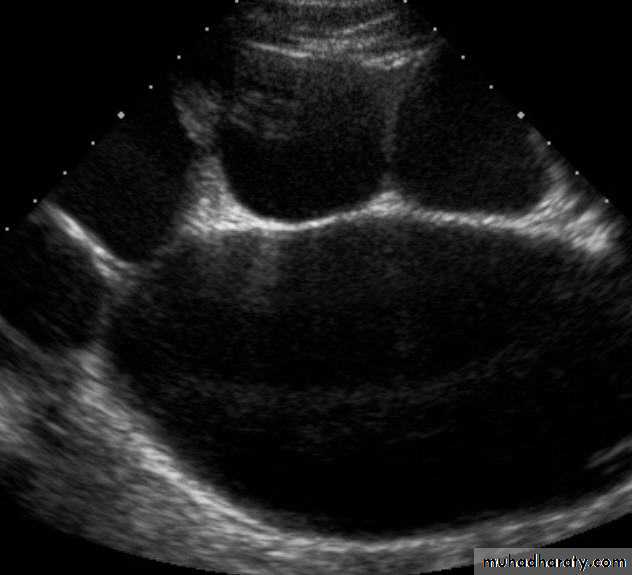

Most common cause of fetal hydronephrosis.

Obstruction at the junction between renal pelvis and ureter.Incidence: 1:1000

US: pre- and post-natal.IV Urography